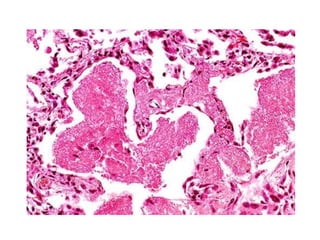

• #10 Infarct & Asprgilloma

• #11 Asperg hyphae lung. Hyphae are at acute angle at each other

• #12 GMS Progressive acute angle dichotomous branching of aspergillus hyphae (Gomori methenamine-silver stain, original magnification600).

• #14 Aspergillosis - Ubiquaitous fungus causing dis- healthy as well as immunocompromised Infection – By inhalation or innoculation ABPA- Hypersenstivity response to inhaled aspergillus Aspergilloma- Fungal ball mc in sinus or within an old tuberculous cavity. It has very small spore whch can penetrate deeper